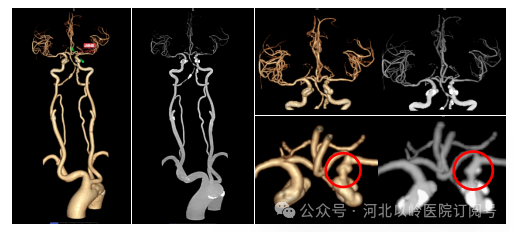

头颈部血管成像技术

对于头颈部血管大范围成像,可同时观察颈总动脉、颈内动脉、颈外动脉、椎动脉以及颅内动脉如大脑前、中、后动脉等是否有动脉瘤形成、是否有斑块形成、斑块性质分析、管腔是否有狭窄、狭窄程度分析、是否存在低灌注等情况,对于脑缺血、脑梗塞可以早期发现、准确定位。